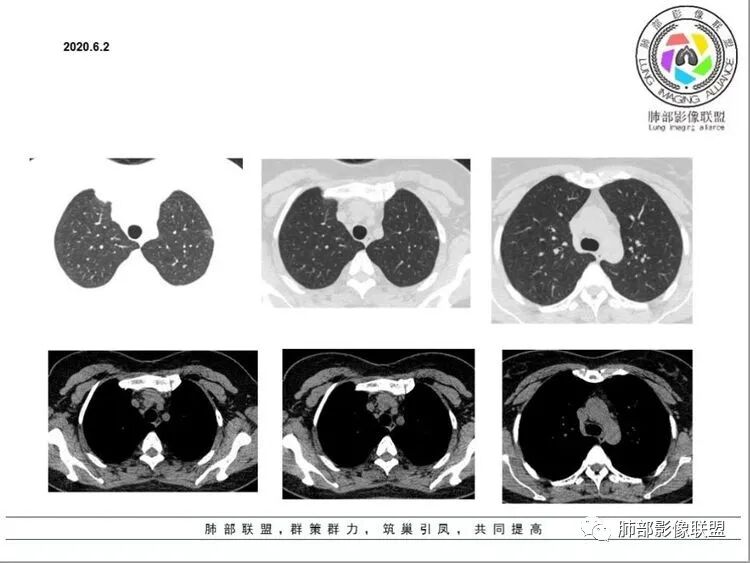

1.中年女性,亚急性病程,以咳嗽、咳痰、胸痛为主。

2.左肺下叶胸膜下团片影及多发小片影,团片影长轴与胸膜平行,周围有模糊的晕,局部平直收缩,支气管近端堵塞,病灶内可见小空洞,空洞内壁光整,邻近胸膜牵拉。

结合肿块周围有多发小片、结节影等类似形态的卫星灶,病灶像炎性,没有游走性,但长时间段抗炎治疗无效,应当想到特殊感染的可能,如隐球菌感染或其他慢性炎症,如结核等。

注意,隐球菌感染出现胸痛的不在少数,敬请留意。

3.患者丈夫有肺结核病史,理应考虑肺结核可能性,但患者病灶周围没有典型树芽,而且病灶的形态较为单一,分布特点都不大符合典型的结核影像学特点。